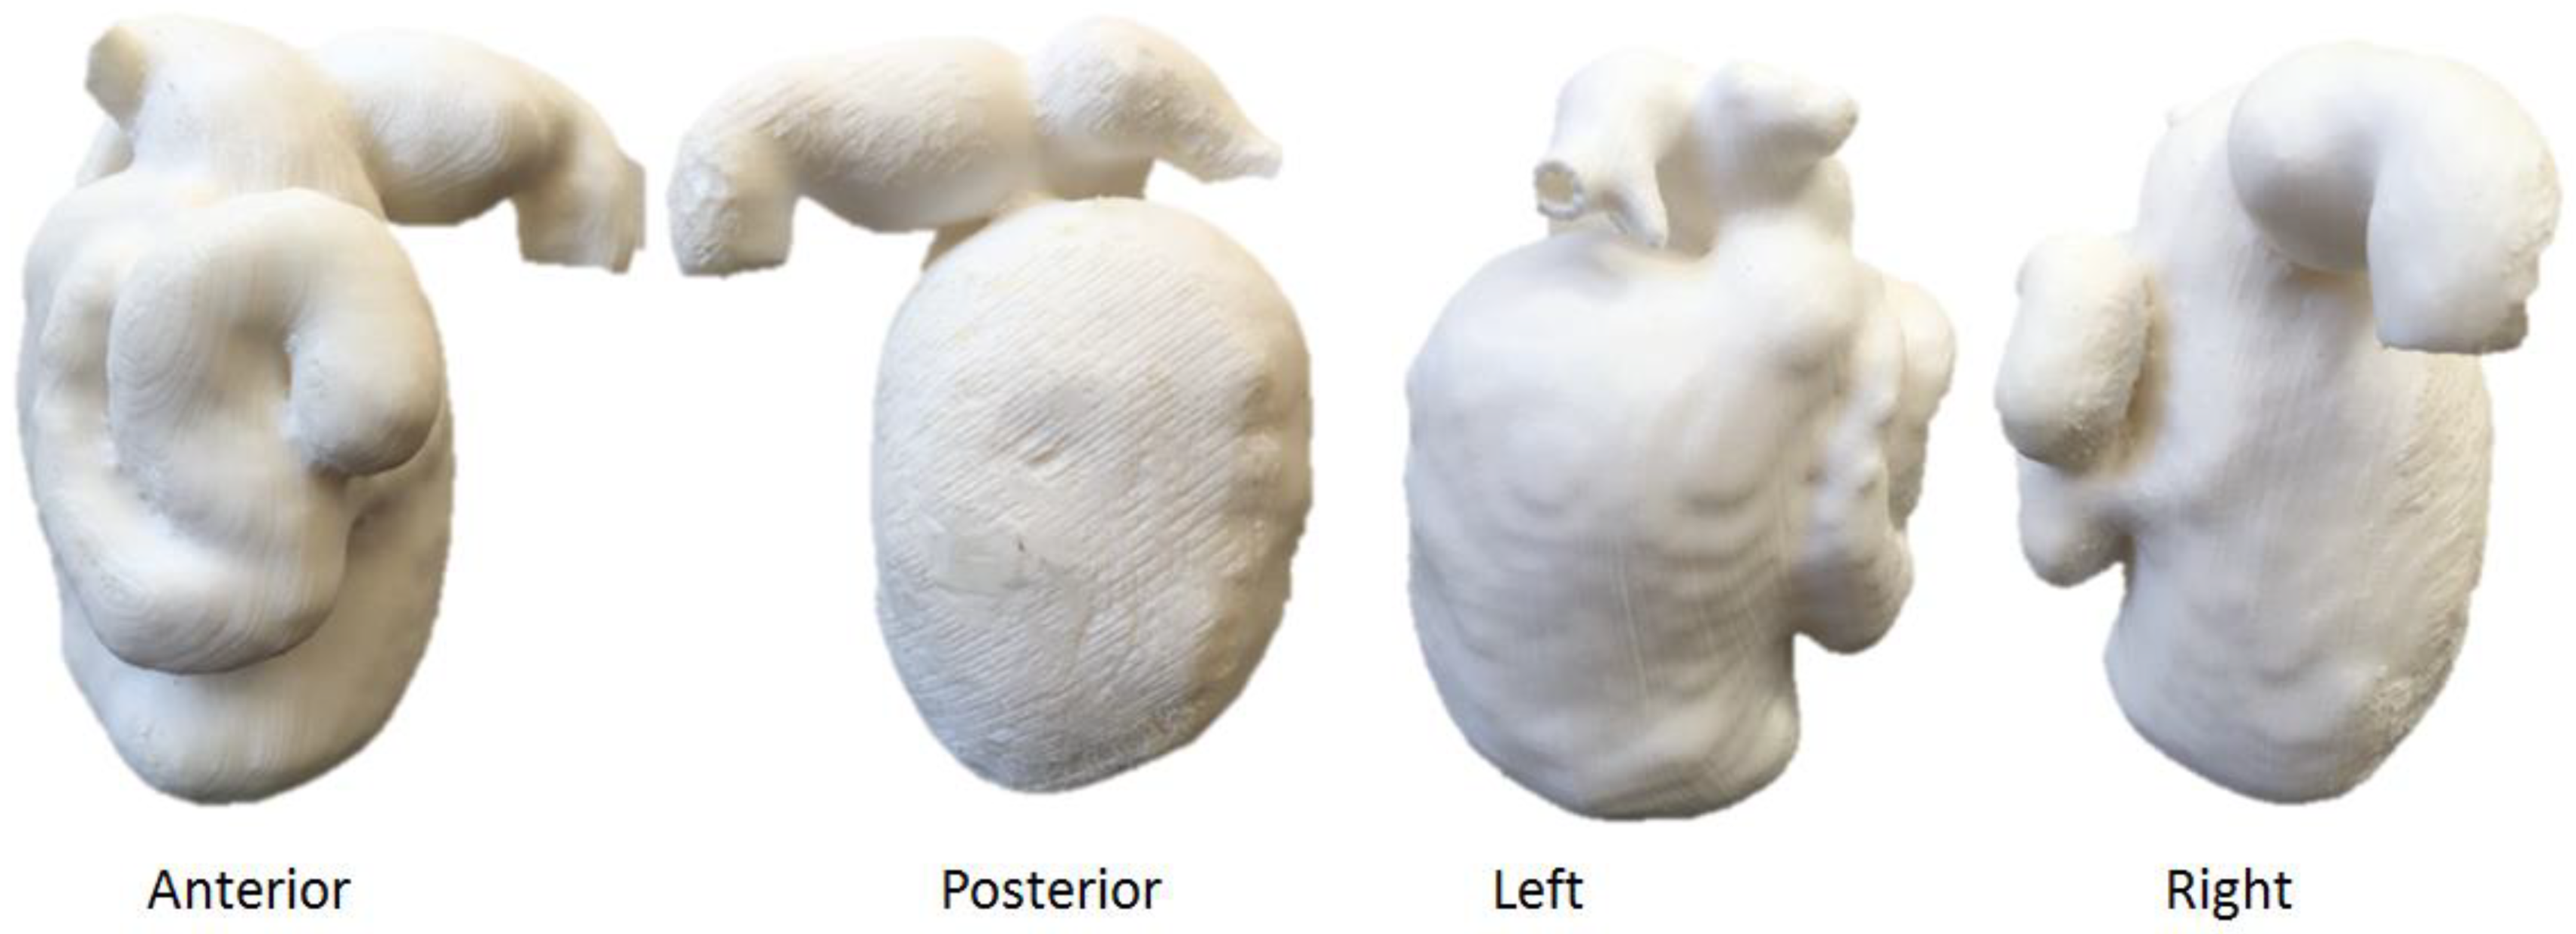

5.3. 3D-Printed Renal Cell Carcinoma Model

- Lupulescu, C.; Sun, Z. The 3D printing of patient-specific kidney models to facilitate pre-surgical planning of renal cell carcinoma using CT datasets. Australas. Med. J. 2021, 14, 211–222. [Google Scholar]

| Kidneys | 1 | CT | Renal cell carcinoma for preoperative planning | Ultimaker 2+ Extended Material: TPU 95A Cost: USD 20 | Model was printed at a resolution of 12.5 μm for the x, y and z-axis planes Time: ~70 h |